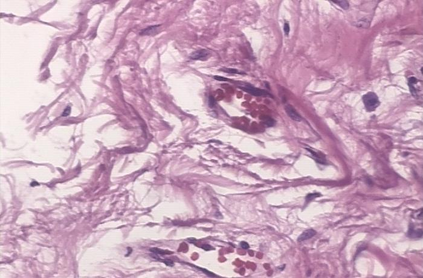

Background: Breast cancer has the highest prevalence in women globally. The classification and diagnosis of breast cancer and its histopathological images have always been a hot spot of clinical concern. In Computer-Aided Diagnosis (CAD), traditional classification models mostly use a single network to extract features, which has significant limitations. On the other hand, many networks are trained and optimized on patient-level datasets, ignoring the application of lower-level data labels. Method: This paper proposes a deep ensemble model based on image-level labels for the binary classification of benign and malignant lesions of breast histopathological images. First, the BreakHis dataset is randomly divided into a training, validation and test set. Then, data augmentation techniques are used to balance the number of benign and malignant samples. Thirdly, considering the performance of transfer learning and the complementarity between each network, VGG-16, Xception, Resnet-50, DenseNet-201 are selected as the base classifiers. Result: In the ensemble network model with accuracy as the weight, the image-level binary classification achieves an accuracy of $98.90\%$. In order to verify the capabilities of our method, the latest Transformer and Multilayer Perception (MLP) models have been experimentally compared on the same dataset. Our model wins with a $5\%-20\%$ advantage, emphasizing the ensemble model's far-reaching significance in classification tasks. Conclusion: This research focuses on improving the model's classification performance with an ensemble algorithm. Transfer learning plays an essential role in small datasets, improving training speed and accuracy. Our model has outperformed many existing approaches in accuracy, providing a method for the field of auxiliary medical diagnosis.